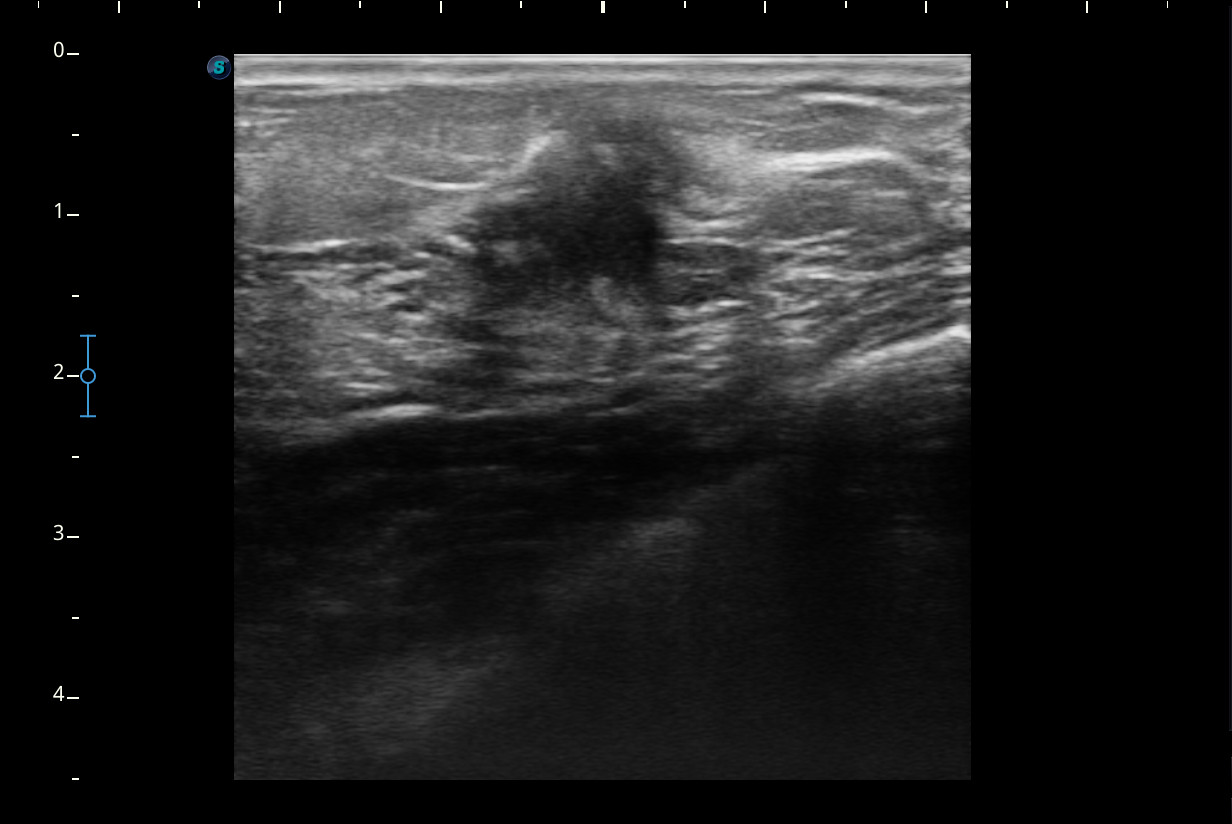

Hallazgos ecográficos

Se visualiza un nódulo mal delimitado, de bordes irregulares y algo espiculados, con captación doppler color sobre todo en periferia y posibles focos centrales de necrosis, compatible con posible neoplasia.